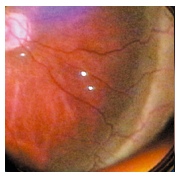

| RETINOPEXIA

EPIESCLERAL:

El Buckling escleral ha demostrado ser efectivo en el tratamiento

de ojos con ROP en etapa 4 o 5, ya sea sólo o como coadyuvante

de la vitrectomía. Sin embargo no es capaz de resolver completamente

la tracción y el proceso proliferativo en la mayoría

de los casos, lo que limita su indicación a casos con DR

por ROP más anteriores.